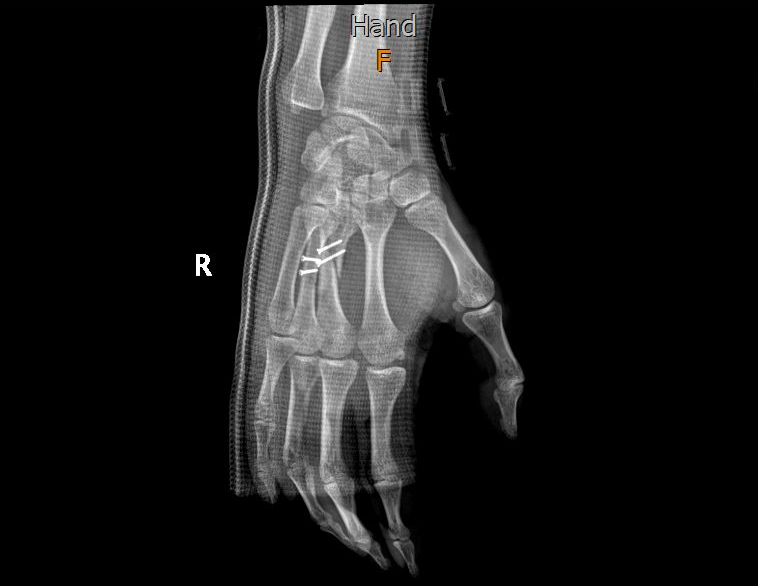

Ngelanjutin cerita yang kemarin.. Besoknya saya ke IGD di RS Mayapada. Ternyata bukan retak saudara-saudara, tapi patah. Tepatnya di tulang Metacarpal 3 dan 4. Patahannya runcing pula.. untung nggak menyebabkan luka dalam yang cukup serius.

Pas jam 3 sore saya dibawa ke ruang operasi yang dingiiin.. begitu masuk sempat langsung nanya sama dokternya, “berarti ntar tiap lewat metal detector bunyi dong, dok?” dan jawaban yang saya inget dia bilang “Harusnya ngga.. kita pasang yang titanium”. Kayaknya ngga sampai 5 menit saya sadar di ruangan itu, karena setelah jawaban dari dokter tadi saya udah ngga ingat apa-apa efek bius total.